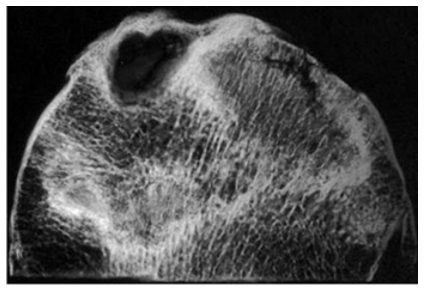

Hydatic Cyst of the Thigh: An Exceptional Location